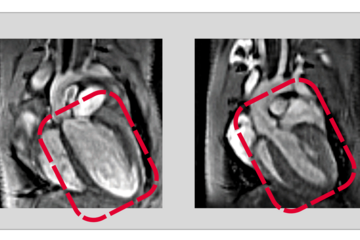

Soni Pullamsetti is involved in the European cooperation on behalf of the Max Planck Institute. The scientist is project leader in the department "Development and Remodelling of the Lung" and has been professor of "Lung Vascular Epigenetics" at the University Hospital in Gießen for a few years. Her focus is on research into arterial pulmonary hypertension. In this disease, the blood pressure in the pulmonary arteries is dangerously high. In patients with this disease, the heart has to pump against the high pressure. "However, for unknown reasons, the hearts of some pulmonary hypertension patients are unable to adapt. This can lead to what is called right heart failure," Pullamsetti said. This could be because genetic variants determine the heart's ability to adapt. Pullamsetti and her team will research possible genetic differences in order to subsequently identify new ways to treat pulmonary hypertension. .